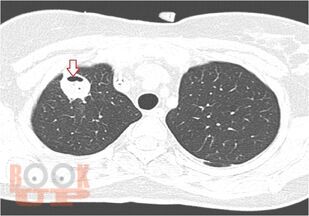

Нагноительные заболевания легких и плевры

В учебном пособии изложены основные варианты нагноительных заболеваний легких и плевры. Дана характеристика, включая этапы развития хирургии нагноительных заболеваний легких и плевры. Приведена классификация, этиология, патогенез каждого патологического процесса. Описаны современные методы диагностики и принципы хирургического лечения. Пособие предназначено для самостоятельной работы студентов лечебного и педиатрического факультета.